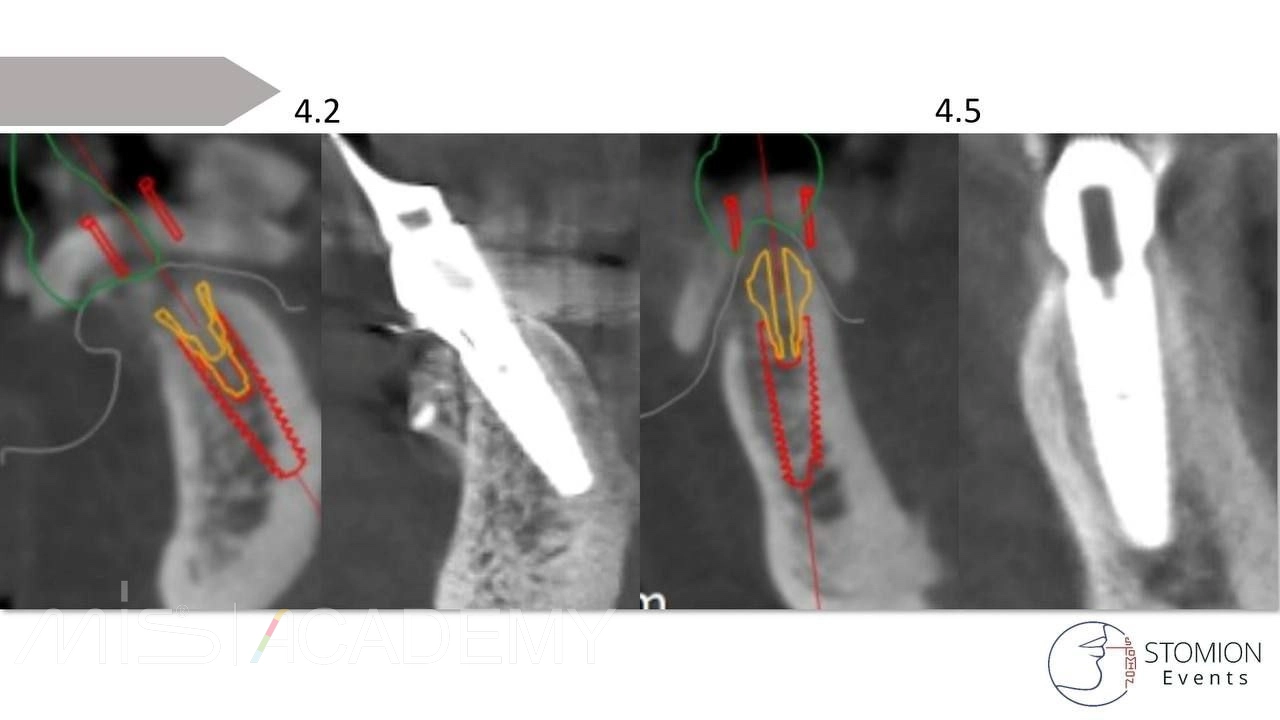

— Навигация полнопротокольная, разборная, накостная.